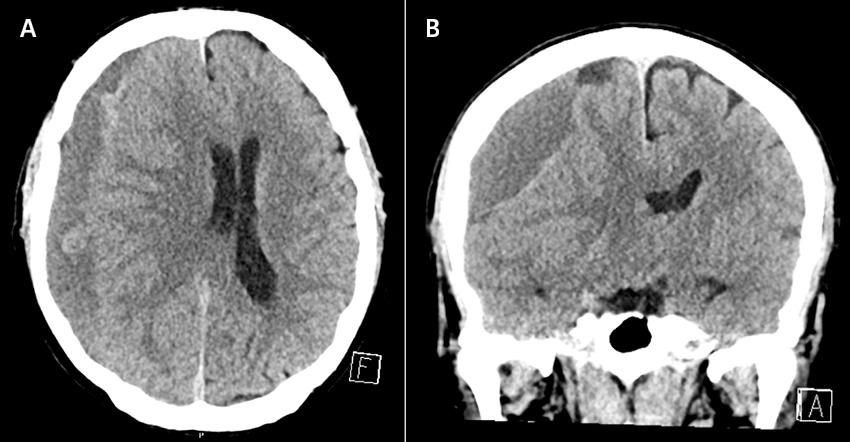

Kroniskt subduralhematom diagnostiseras med nativ DT av hjärna. Typisk bild är en låg- (< 30 Hounsfield-enheter [HU]) eller isoattenuerande (30–60 HU) vätskeansamling längs hjärnans konvexitet, där även högattenuerande (> 60 HU) inslag kan förekomma [5]. Äldre blödningar brukar vara mer lågattenuerande. Diagnosen kan även påvisas med magnetkameraundersökning, då ofta som bifynd när andra diagnoser misstänkts.

Datortomografi av hjärna som visar ett högersidigt kroniskt subduralhematom i axial (A) och koronar (B) projektion.